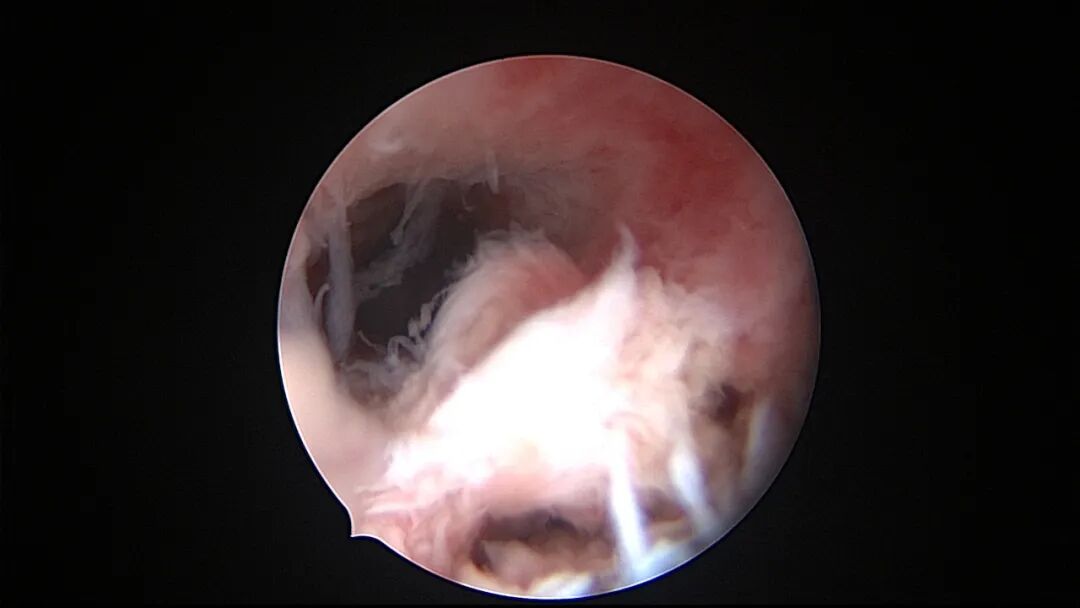

6例外院取环失败,子宫假道

为了宫腔镜手术平稳顺利进行,宫腔镜术前准备及安全评估非常重要,尤其是充分的安全评估能有效减少并发症的发生。阴道情况:萎缩、纵膈、斜膈等可能导致扩阴器置入困难。肥胖病人、高个子病人阴道很深,宫颈可能难以暴露;宫颈情况:绝经后病人宫颈萎缩、狭窄、坚硬,加之穹隆展平,宫颈难以夹持、难以扩张;宫颈管弯曲、宫颈肌瘤、巨大息肉、粘膜皱襞隐窝、巨大纳囊等,可能阻挡宫腔镜进入宫腔;子宫情况:子宫萎缩,宫腔狭小,子宫极度前屈、后屈、侧屈等极端位置常常导致宫腔镜置入困难;既往盆腔手术史:子宫与盆腔器官粘连可能导致子宫极端位置,或者宫深超出预期。近期手术情况:外院取环失败、人流不全、宫腔探查或试图分粘中途放弃等病人,子宫可能存在假道、穿孔或盆腔积血等损伤。这类病人评估重点:前次手术医院级别、既往分娩情况、安环多少年、月经情况、闭经或绝经时间、手术日期、手术时间长短、是否麻醉、术后有无腹痛、有无阴道出血、B超情况、腹部平片、血糖血压等。宫腔镜术前需再次复查B超,手术医生到B超室了解子宫位置、大小、有无损伤、节育环种类及位置、是否嵌顿、盆腔有无积液等细节。